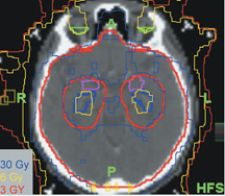

cIso-dose lines for whole brain treatment plan using helical TomoTherapy. A buffer zone of ~ 1cm around the hippocampus (red lines) with a lower dose is needed in order to keep the dose to the hippocampus as low as possible.

Dr. Mehta added that his brain tumor patients benefit from the conformal avoidance that the Hi·Art System allows. Conformal avoidance is used in cases where the tumor boundary cannot be easily defined. Rather than trying to map the precise area to be treated, clinicians instead map out critical structures that must be avoided. “Helical delivery allows for superior dose conformance and critical structure avoidance. The TomoTherapy unit is capable of delivering helical fan-beam IMRT projected through 51 beam angles.”

Dr. Mehta and Deepak Kuntia, M.D., along with Hazim Jaradat, Ph.D., are pioneering optimal conformal avoidance to critical structures in the brain. Specifically, they are developing TomoTherapy treatment plans to conformally avoid the hippocampus, the structure that houses memory function in the brain. Dr. Mehta not only wants to eliminate his patients’ cancer, he wants to preserve their quality of life for the future, sparing patients’ memory, speech, vision and hearing as much as possible. He believes that conformal avoidance with helical IMRT can do just that.